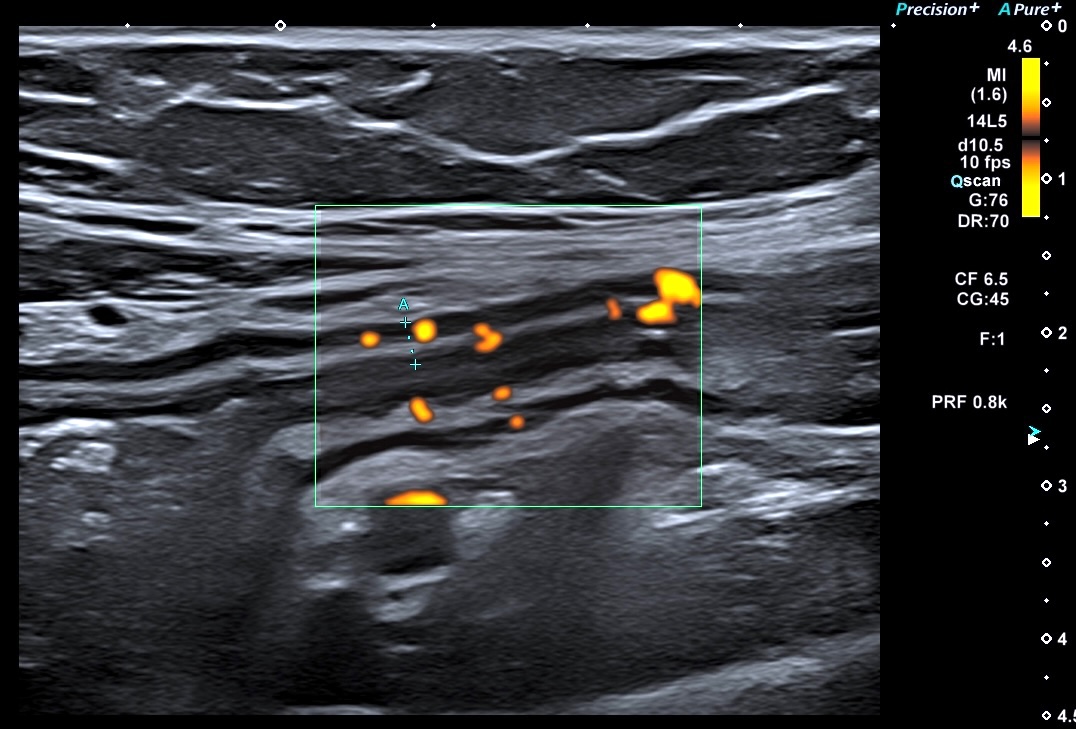

Le doppler est souvent limité à la paroi (Limberg 1 et 2), la graisse peu ou pas infiltrée

*Paroi antérieure et postérieure accolées, hypoéchogènes et doppler *

Surface irrégulière ulcérée